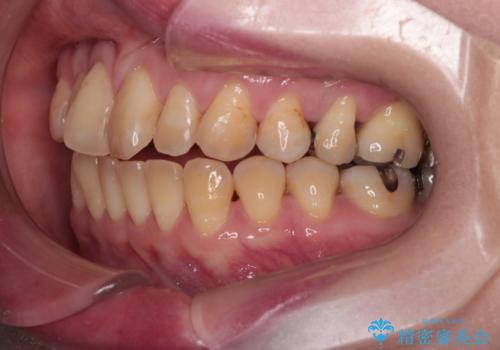

- 上の前歯の捻れと、前歯で物が噛めないことを主訴に来院されました。

前歯の翼状捻転とオープンバイト傾向だったため、インビザラインにて矯正を行いました。右下の奥歯は保存不可だったため、抜歯を行いインプラントにて修復を行なっています。

翼状捻転はインビザラインでは苦手とする動きですが、ここまで綺麗に治すことができました。